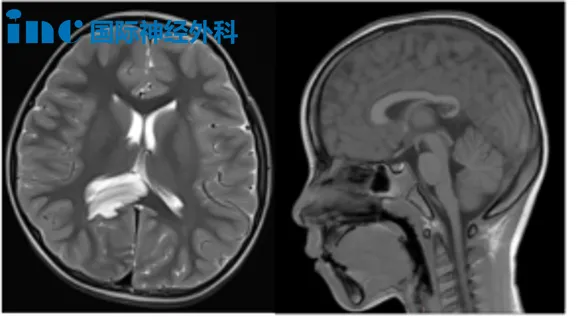

霖霖意外发现右侧海马及右顶叶占位病变,初期未呈现明显临床症状。考虑到患儿年龄因素,家属最初选择保守观察方案。然而肿瘤并未保持静止状态,在不到一年时间内,丘脑区已出现肿瘤推挤效应。

面对这一进展,拥有40余年神经外科经验的巴特朗菲教授如何评估?10月22日,家属带患儿至苏州大学附属儿童医院进行面诊。针对家属疑问,教授解释道:"此类肿瘤不会自行停止生长,年度复查将显示体积增大。另一关键问题是肿瘤可能发生基因突变,向更高级别恶性转化。此外,肿瘤毗邻颞叶内侧部,该区域病变易诱发癫痫发作......"

类似情况也出现在8岁患儿小航身上。影像检查显示右侧丘脑与基底节区占位病变,病灶尺寸约4.0cm×4.7cm×4.8cm,高度怀疑为弥漫性胶质瘤。